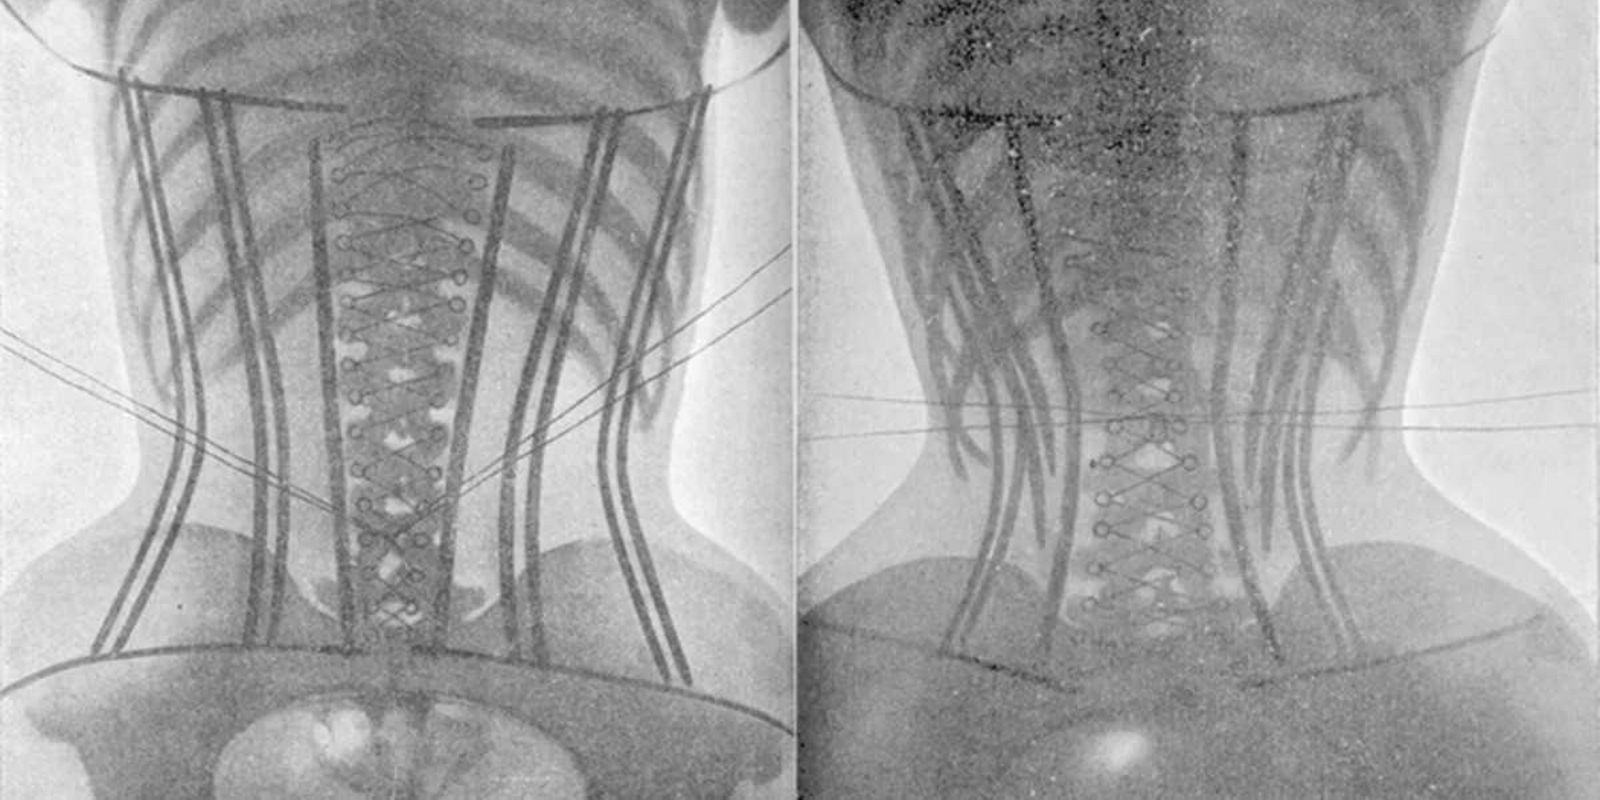

- corset

- waist trainer

- corset

- waist trainer